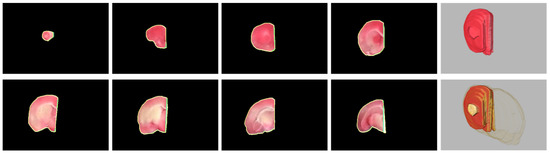

3. Hemisphere Segmentation

3.1. Challenges

- Due to the manual placement of the rat brain slices, the midline is randomly oriented, not vertically.

- The rat brain can be seriously distorted due to the infarction of the induced stroke so that the midline is convoluted.

- The midline exhibits a similar color tone to its surrounding tissues and is visible in short segments to the naked eyes.

- There are merely few anatomically salient structures around the midline that can provide meaningful information for the identification.

4.4. Evaluation of Rat Hemisphere Segmentation